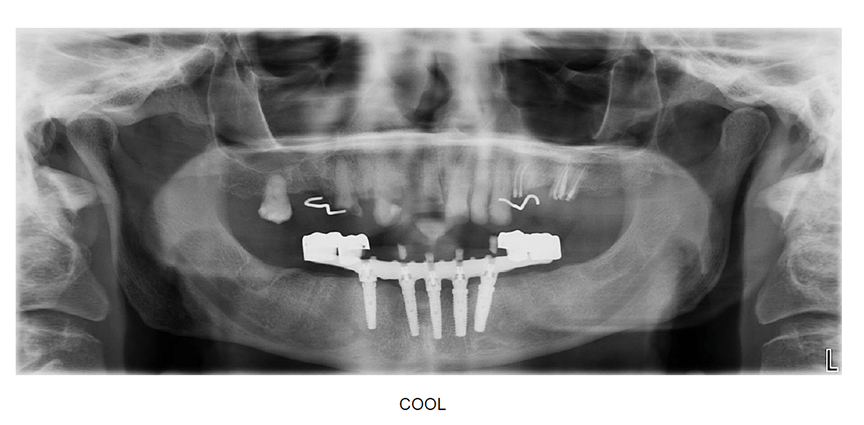

Titanium CAD CAM bar with processed high impact acrylic fixed hybrid

Before and After – full mouth implant reconstruction titanium bar and acrylic